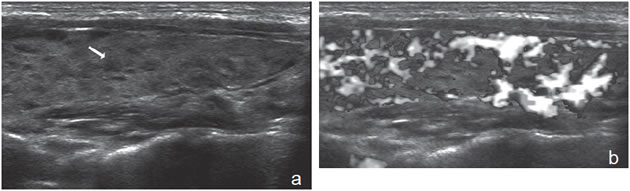

encapsulado (flecha abierta). Otra apariencia típica es la de un nódulo no encapsulado, que contiene múltiples espacios anecogénicos (coloide), separados por finos septos, que le da un aspecto espongiforme (Figura 18a) o en “panal de abejas”7. Los espacios quísticos pueden ser de tamaño variable, y observarse focos hiperecogénicos en las aéreas quísticas que contienen coloide o focos ecogénicos lineales en las interfases entre los espacios quísticos y los tabiques o la pared; pueden ser hipo, iso o hipervasculares.

Los componentes quísticos pueden ser muy pequeños y sólo detectarse con equipos de alta resolución. Este aspecto espongiforme puede aparecer más acentuado cuando los espacios quísticos son de mayor tamaño; si aparece hipervascularizado, a simple vista puede simular una neoplasia quística (Figura 18b y c). Puede predominar el componente quístico, y sin embargo, el componente sólido conservar el aspecto espongiforme (Figura 18d).

Figura 18. a) Tres nódulos coloideos, con aspecto

espongiforme, isovasculares al “doppler color”.

La flecha indica un espacio quístico y la flecha

abierta indica un pequeño tabique hiperecogénico.

La alternancia de ambos, forma este aspecto

en “panal de abeja”; b) y c) Nódulo coloideo

con aspecto espongiforme, con espacios quísticos

de mayor tamaño, de forma redondeada, que

aparece hipervascularizado en las áreas sólidas;

d) Nódulo coloideo mixto, predominantemente

quístico, en que el componente sólido conserva el

aspecto espongiforme (flecha abierta).